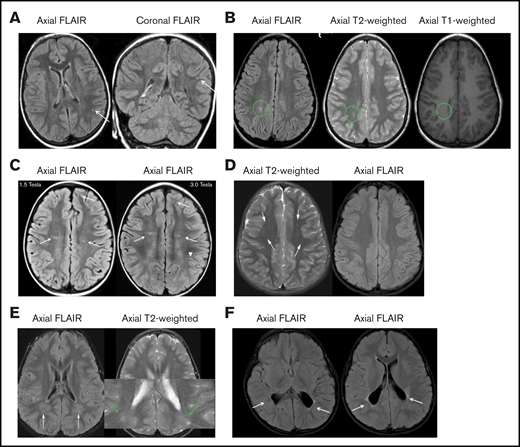

Pooled analysis of the 10 studies documenting TCD measurement before and after hydroxyurea therapy in children with HbSS or HbSβ0thalassemia. This meta-analysis demonstrates the average drop in TCD measurement after starting hydroxyurea therapy of 21 cm/s (95% confidence interval [CI], 14.8-29.0). The plot also suggests that the decrease in TCD measurements can be seen as early as 3 months after the start of hydroxyurea therapy with a sustained impact of hydroxyurea therapy on decreasing TCD measurements for at least 36 months. The analysis is updated from a previous one by DeBaun and Kirkham,58 plus additional references.51-57,59,60,165 ♦ represents the pooled estimate from a random-effect model, the edges of the diamonds represent the 95% CI; ▪ represents individual studies. MTD, maximum tolerated dose.

To obtain additional evidence that hydroxyurea decreases TCD measurements, the panel reviewed 10 studies in children with HbSS or HbSβ0 thalassemia who had TCD measurements at baseline and several months after starting hydroxyurea therapy (Figure 4). The decrease in TCD measurements can occur as early as 3 months after starting hydroxyurea therapy with a sustained impact of hydroxyurea therapy on decreasing TCD measurements for at least 36 months. In a pooled analysis of 10 studies, the average drop in TCD measurement after starting hydroxyurea, 21 cm/s, was a clinically relevant decline (Figure 4).